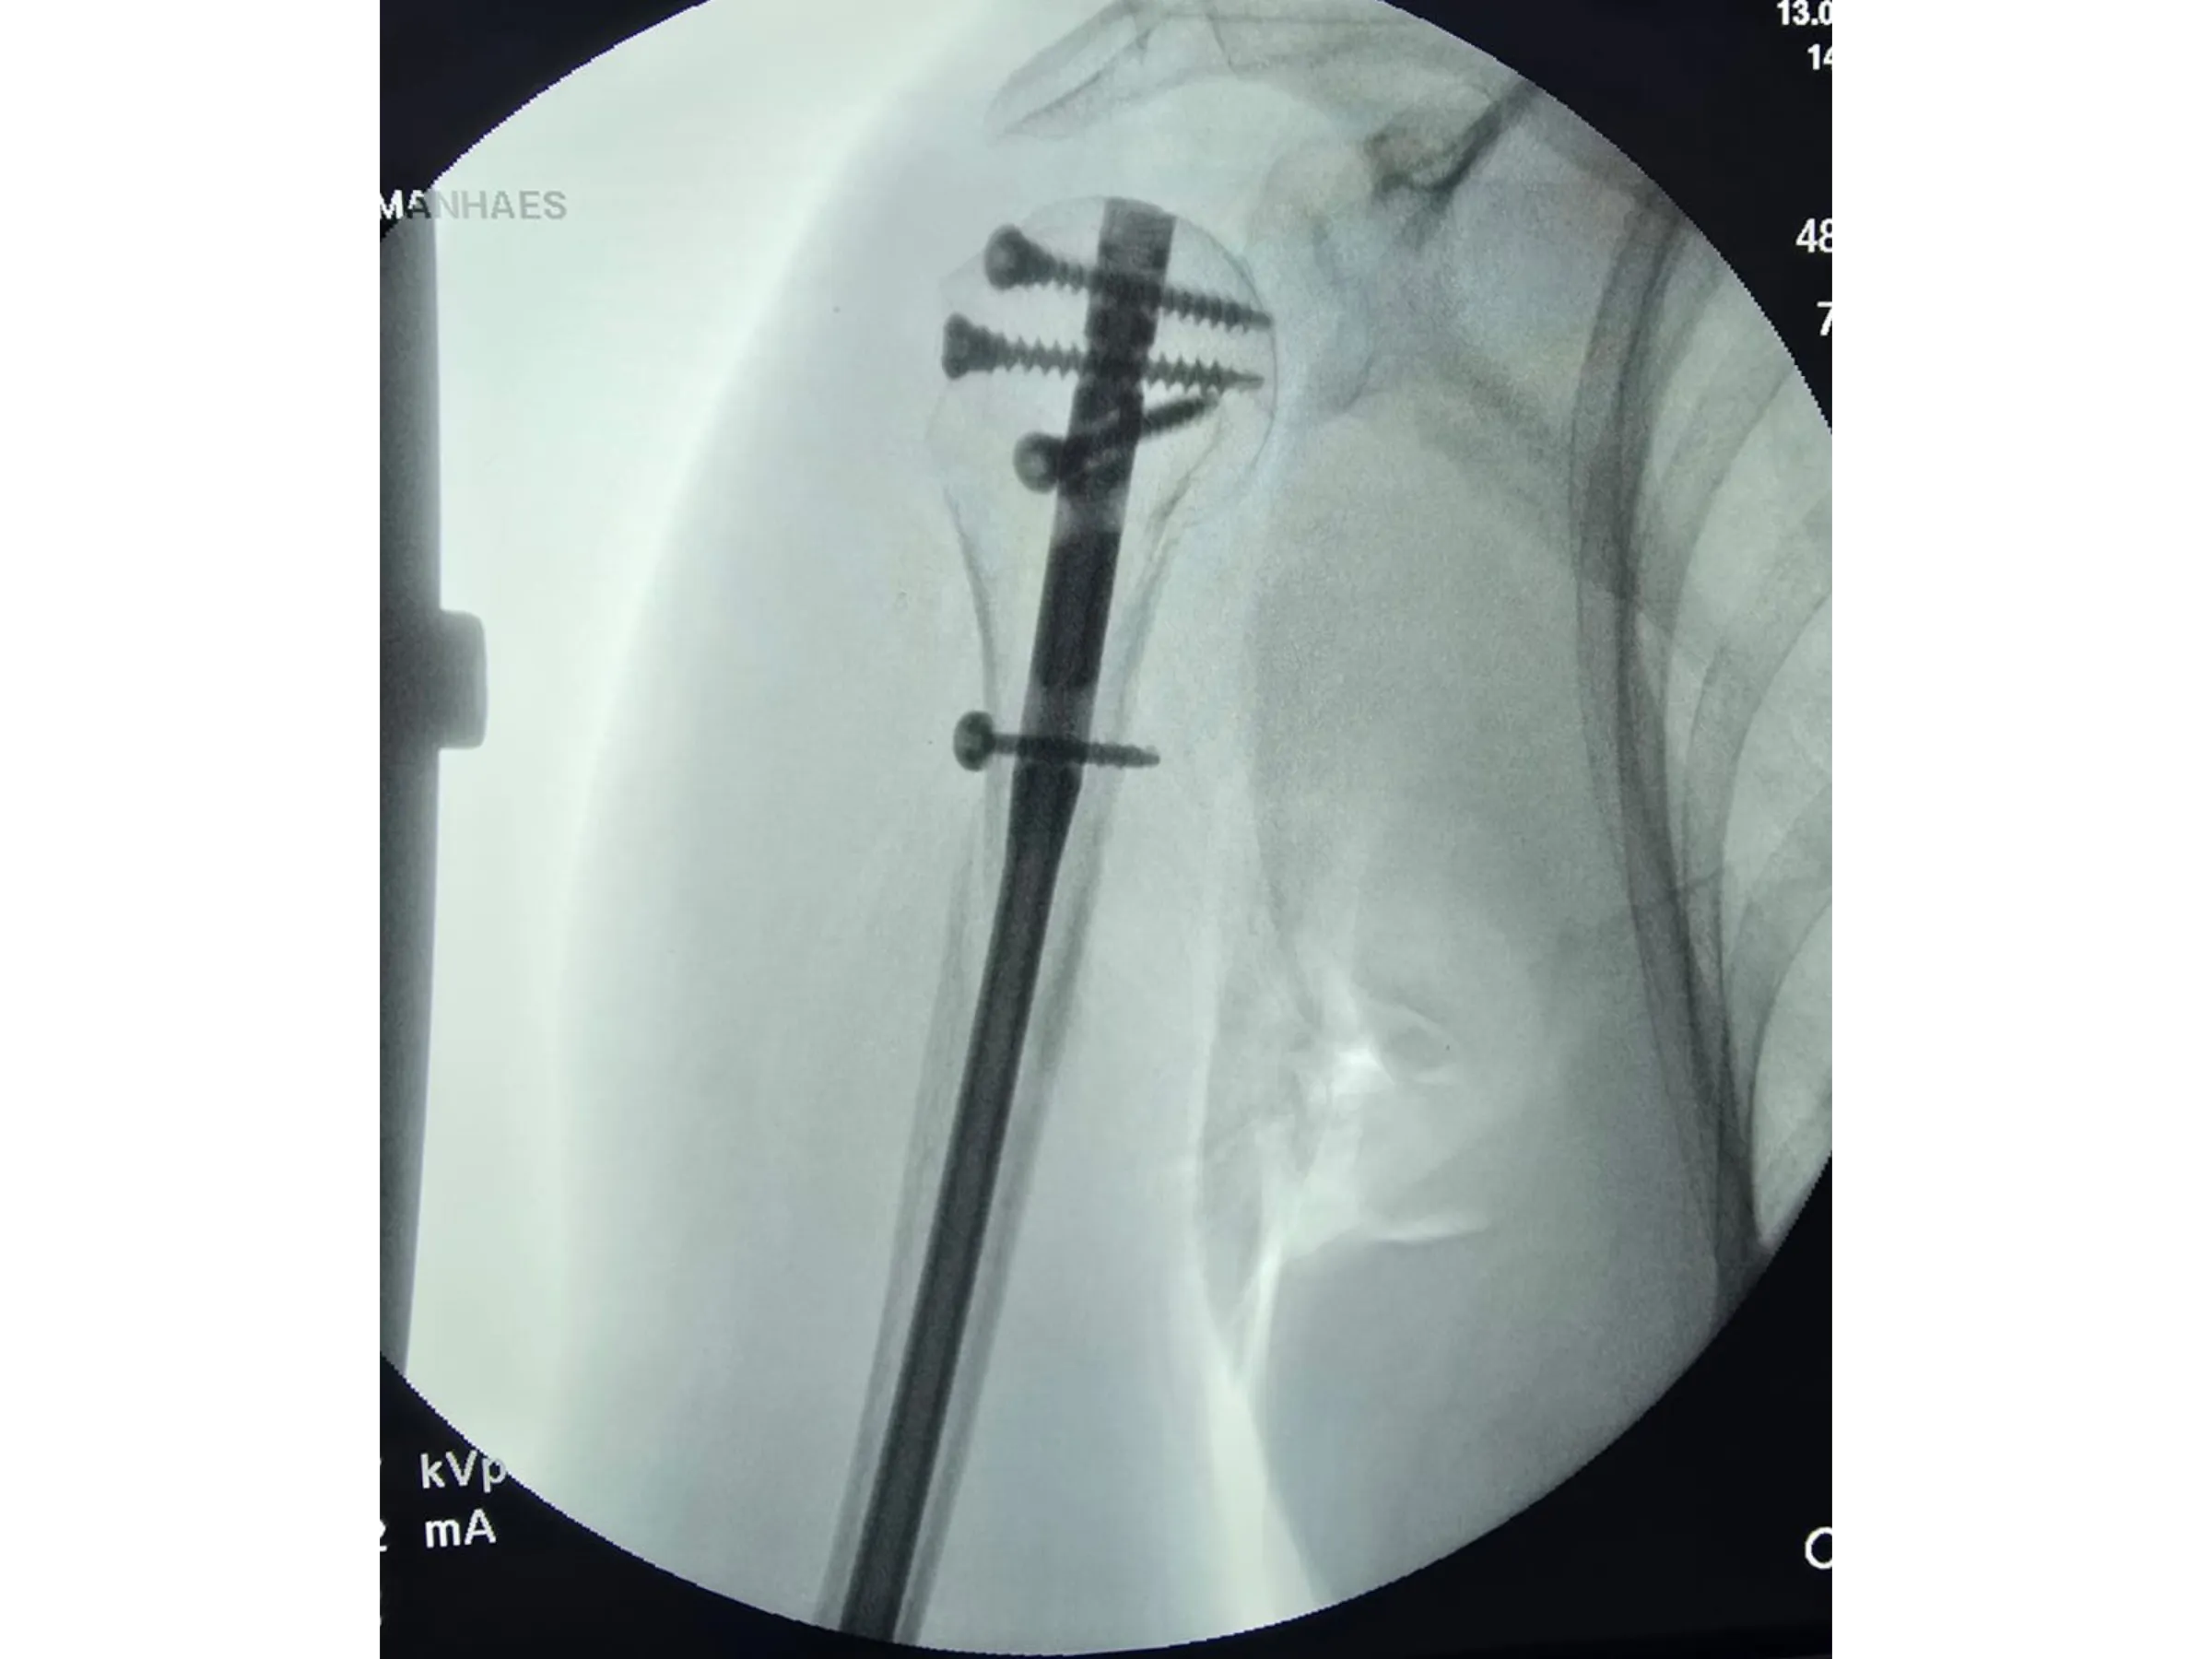

- Insertion of a long intramedullary rod with proximal and distal locking.

- Stable Intramedullary Fixation: Insertion of a long rod with multiple locking screws, including metaphyseal screws.

- Rigorous Fluoroscopic Control: Anteroposterior and lateral images to ensure parallelism and precision of the implants.